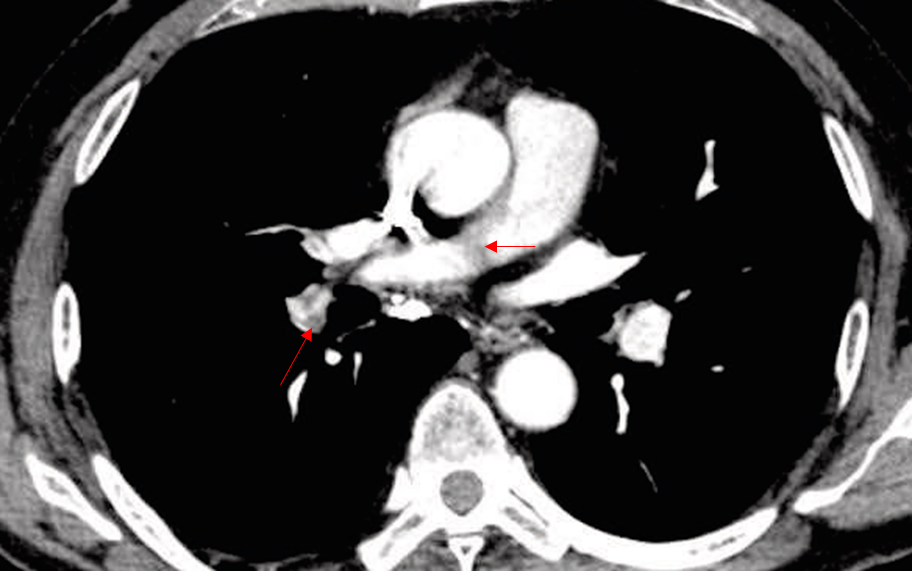

Img | CXR: No remarkable findings CT: Filling defects possibly at Rt. main and lobar pulmonary artery |

최근 femur 골절 및 수술력이 있는 급성 호흡곤란 환자의 CT상 pulmonary artery 내부에 filling defect가 관찰되므로 PTE로 진단한다.

• PTE 진단의 1st line은 pulmonary artery 내부를 조영증강하는 CT angiography이다. CT상 Rt. main 및 lobar pulmonary artery에 어두운 filling defect가 확인되는데, 상기 임상양상과 종합할 때 thrombus일 가능성이 매우 높다.